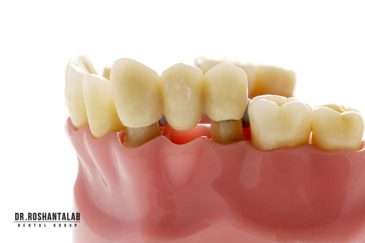

🔸 ایمپلنت دیجیتال و ساخت روکش دیجیتال

طراحی لبخند هالیوودی با متدهای لمینت سرامیکی دندان و کامپوزیت ونیر در کنار اصلاح فرم، خدمات بلیچینگ و روکش دندان، زیبایی چهره شما را تکمیل میکند.ترمیم دندان

از عصب کشی و درمان ریشه دندان گرفته تا جراحی لثه و کشیدن دندان، تمامی مراحل توسط متخصص ترمیم دندان مدیریت میشود. ارائه باکیفیتترین خدمات ترمیم دندان برای سلامتی شماست.کاشت ایمپلنت فوری دندان